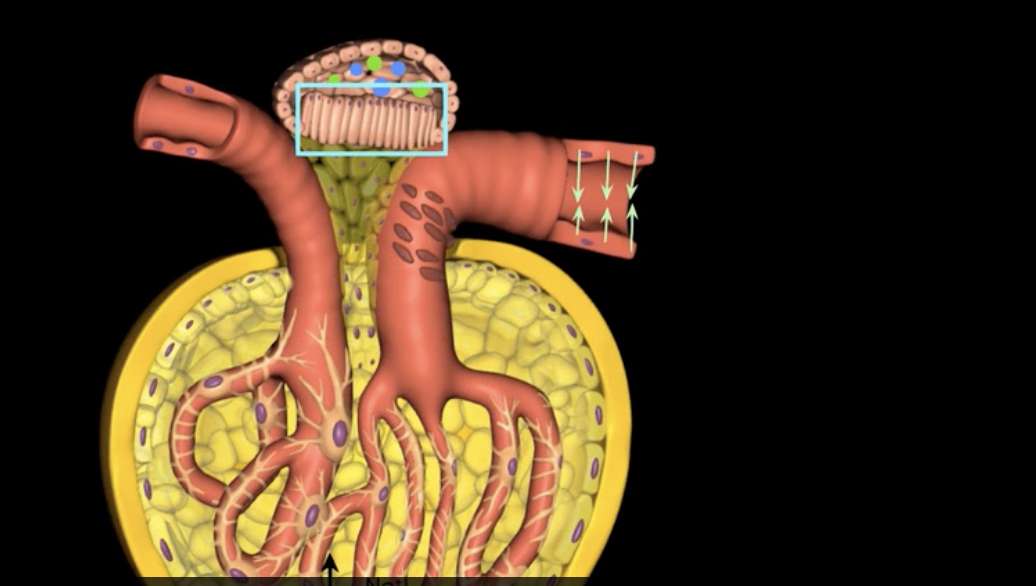

blue: visceral layer

red: parietal layer

simple squamous

the parietal layer consists of [ ] epithelium that surrounds the glomerulus

capsular space

pink: podocyte

purple: pedicels

filtration slit

filtration membrane

fenestrated capillaries + podocytes = [ ]